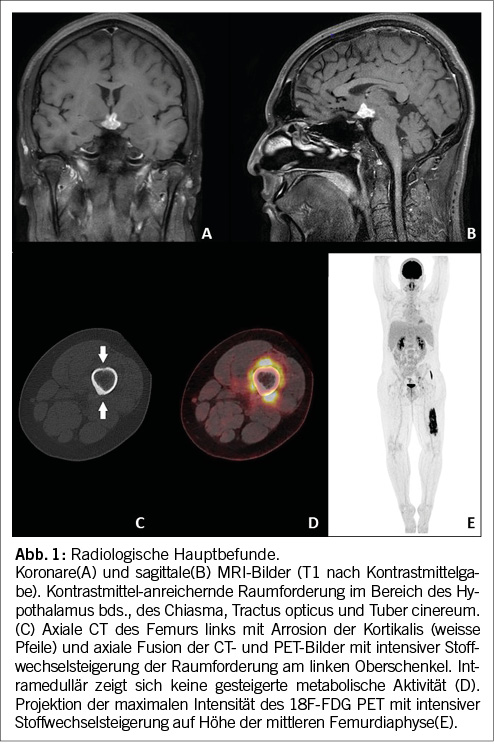

Aufgrund des nicht adäquat substituierten Panhypopituitarismus erfolgte zur Standortbestimmung ein MRI des Neurocraniums. Hier konnte eine atrophierte Hypophyse mit fadendünnem Hypophysenstiel und fehlendem Hypophysenhinterlappen-Signal dargestellt werden. Des Weiteren bestand eine deutlich Kontrastmittel-aufnehmende Raumforderung im Bereich des Hypothalamus, des Chiasmas und Tractus opticus beidseits (Abb.1A und B).

Diese Befunde eines jungen Patienten mit Diabetes insipidus mit progredientem Hormonausfall, atrophierter Hypophyse mit fadendünnem Hypophysenstiel und deutlich Kontrastmittel aufnehmender Raumforderung im Hypothalamus und atraumatischen Knochenschmerzen passen zu einer Manifestation einer multisystemischen LCH, weshalb wir im nächsten Schritt ein Ganzkörper 18F-fluorodeoxyglucose (FDG)PET/CT durchführten. Die Untersuchung zeigte eine intensive FDG-Aufnahme in der hypothalamischen Raumforderung. Im Bereich der beklagten Schmerzen (Femurdiaphyse links) fand sich eine intensiv FDG-avide Raumforderung in der Muskulatur rund um die Femurdiaphyse mit lokalen Arrosionen der angrenzenden Kortikalis, ohne gesteigerte Stoffwechselaktivität im Knochenmark (Abb. 1C und D). Diese Läsion am Femur links war gut zugänglich für eine CT-gesteuerte Biopsie.